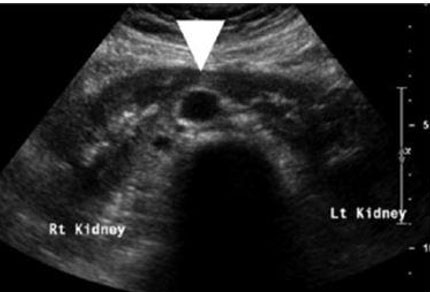

The fetal urinary tract has a very intricate development process and is the most common system affected by congenital defects [1]. Congenital anomalies of the kidneys and the urinary tract (CAKUT) account for approximately 30% of all congenital malformations. Abnormalities can affect the upper urinary tract such as the kidneys and the ureters and the lower urinary tract, impacting the bladder and the urethra which will then affect the amniotic fluid volume. Congenital anomalies of the kidneys and the urinary tract causes include genetic etiologies, maternal diet, and fetal exposures [2]. The antenatal detection of the anomalies, which is at 73.87%, has helped improve outcomes [3]. The most used imaging tool is ultrasound, furthermore it is standard practice to visualize the kidneys and the bladder during the second trimester ultrasound in pregnancy (Figure 1A and Figure 1B) [4]. The spectrum of outcomes for these patients ranges from no clinical significance to more serious outcomes such as pulmonary hypoplasia and end-stage renal disease [1],[5]. While each malformation has a different male to female ratio, CAKUT impacts more males [3]. A multidisciplinary care team is important when diagnosing, managing, and treating CAKUT. In this review, we will discuss the relevant embryological process and discuss different anomalies (Figure 1A and Figure 1B).

Figure 1: Normal ultrasound views of the kidneys. (A) Coronal views in a 12-week fetus, (B) axial view of the kidneys at 20 weeks and 6 days [26]. Radiological images were obtained from open-access article distributed under the terms of the Creative Commons Attribution License (CC BY) [26].